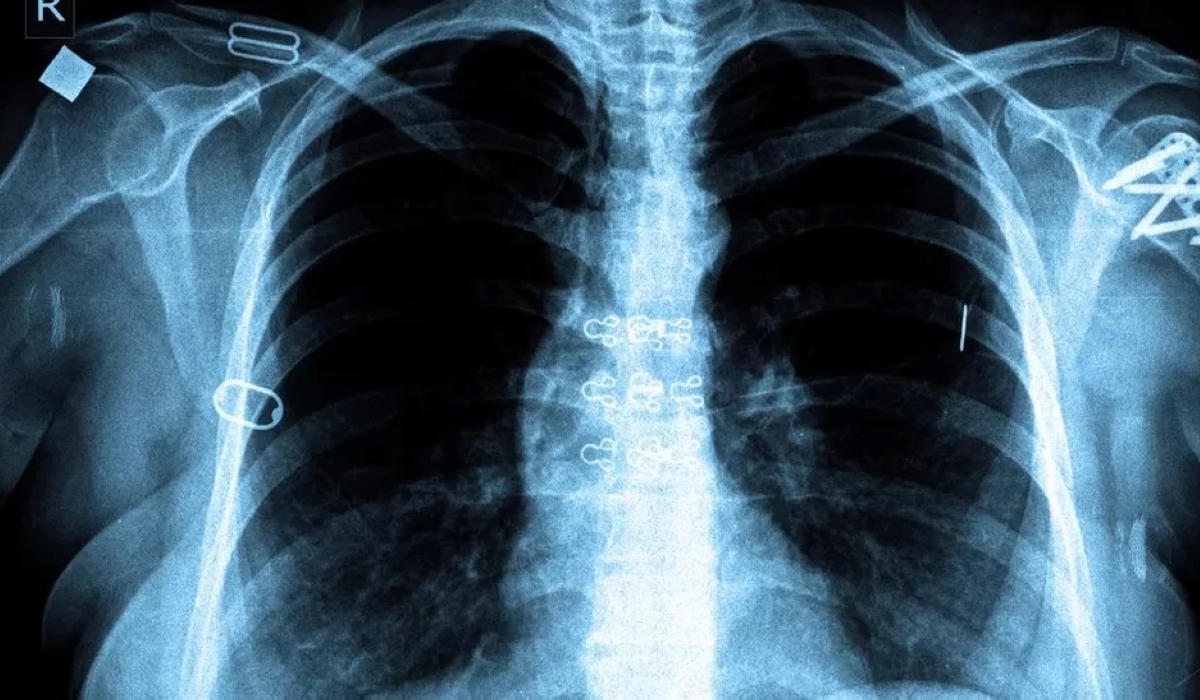

Tuberculosis (TB) is the most common opportunistic infection and one of the leading causes of death among people living with HIV(PLHIV) worldwide. The lifetime risk of developing active TB in a person who is not infected with HIV is about five to 10 percent lower as compared to a person living with HIV. Globally, the risk of developing active TB is 20 times higher among people living with HIV than those who aren’t. However, around 6,000 patients with active TB are registered every year. Compared to its immediate neighbors, Rwanda has a relatively low TB incidence, currently at 58 infections per 100,000 people, a steady decrease from 96 infections per 100,000 people in 2000. TB is caused by a germ called Mycobacterium tuberculosis. The germs are spread from person to person through the air when a person with pulmonary TB coughs, sneezes, laughs, or sings. TB germs can remain inactive in the lungs for a long period but can still be passed on to others. However, if these germs become active and multiply, the patient will develop TB. These germs usually attack the lungs, but they can also attack any part of the body, such as the kidneys, brain, spine, skin, and others. TB symptoms include prolonged fever, chronic cough, drenching night sweats and weight loss. People living with HIV are more likely than others to contract TB because HIV weakens the immune system and causes depletion and dysfunction of CD4 cells making it harder for the body to fight back infection. The ‘World Health Organization End TB Strategy’ prioritizes preventive treatment among people living with HIV. Additionally, the 2021 Political Declaration on HIV/AIDS states that to reduce TB-related morbidity and mortality among people living with HIV, 90 percent of them should receive TB preventive treatment. The Ministry of Health through RBC recommends the implementation of TB preventive therapy to people living with HIV. While TB vaccination does not prevent infection, it protects many against the most severe forms of tuberculosis (milliary and TB meningitis). TB vaccination is compulsory for newborns and infants exposed to HIV if they are asymptomatic and infants with signs and symptoms of clinical AIDS. However, it is recommended that TB vaccination is postponed in premature babies and newborns whose weight is below 2.5 kilograms. A combination of HIV and TB poses challenges in both the diagnosis and treatment processes. To increase TB detection in HIV-infected individuals, healthcare providers are advised to screen TB by asking patients if they have been coughing for more than three weeks, have extreme weight loss in the past three weeks, have chest pain, or whether they are having excessive night sweats or have contact with someone who contracted TB. If the patient has any of the above signs, a few exams are done in the laboratory. The laboratory exams include sputum exams, chest x-ray, gen expert, CT scan, and culture from potentially infected organs. Besides the screening, the government has poured its resources into ensuring the treatment of all persons living with HIV regardless of age as well as identifying those cases who do not know their status. Additionally, the government provides TB preventive therapy to household contacts of those persons staying with a person with TB. Currently, across the country, more than 69 GeneXpert using molecular testing technology machines are in use for TB diagnosis in all hospitals and some health centers with high TB rates. What should you do when you have TB and live with your family? Once you know you have active TB, take TB drugs right away because you need less than two weeks of consistently taking the medication as prescribed by the doctors to stop spreading the germs. Ensure that your mouth and nose are always covered with an N95 face mask. You can also try to drink warm liquids to avoid coughing a lot since sneezing and coughing can potentially spread germs. As a patient, ensure that you spend less time in shared places like seating rooms, dining, bathrooms, and kitchens. The people sharing a home with a patient and the patient himself are advised to regularly wash their hands and wear gloves. How can you support someone with active TB that shares your home? It is advisable that the person with active TB is put in a well-ventilated and isolated room seven days before and another seven days after taking TB drugs. You can provide the patient with some fruits and vegetables like oranges, mangoes, sweet pumpkin, carrots, tomatoes, nuts, and seeds since they are excellent sources of Vitamin A, C, and E which are highly required. Dr. Julius Kamwesiga, Medical Director, AIDS Healthcare Foundation (AHF)